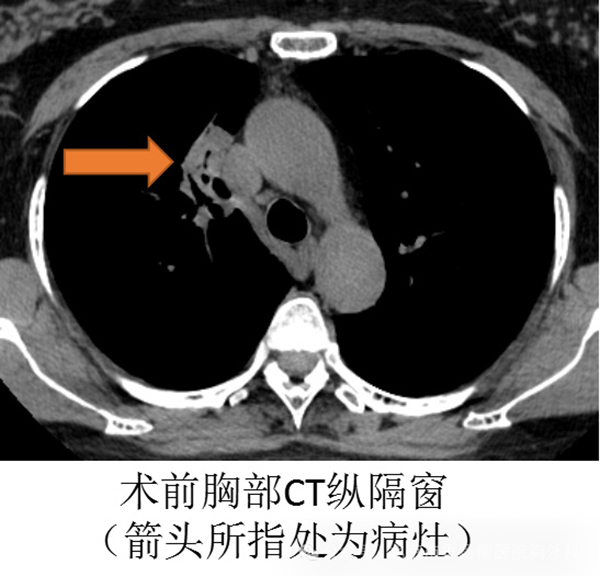

体检完毕,接着继续就诊,做完了胸部增强CT,但还是不能明确良恶性,最终还是需要病理明确,现在的活检方式多样,常用的有CT引导下肺穿刺,不过她的病灶沿着气道分布,CT引导穿刺极有可能穿入邻近的血管、气管,出现气胸、血胸、咯血甚至空气栓塞等危及生命的并发症。

面对患者及家属的期待,垂杨柳医院胸外科团队不敢有丝毫松懈,术中认真观察着气管每一支的异常,并利用胸外科常规开展的EBUS-GS-TBLB技术,应用气管镜下超声小探头,明确探查到右肺上叶前段亚段外侧的病灶,充分进行活检。